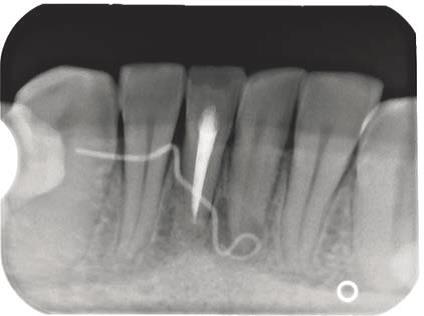

Ryc. 10. Zdjęcie rentgenowskie zęba 31 oraz umieszczonego w przetoce ćwieka gutaperkowego.

Źródło: Olczak K, Pawlicka H. Zastosowanie rentgenodiagnostyki w endodoncji. Mag Stomatol. 2019; 9: 30.

Jeszcze w stosunkowo niedalekiej przeszłości pokutowało wśród pacjentów (i niestety również wśród niektórych lekarzy dentystów) przekonanie, że zęby będące przyczyną stanów ropnych należy usunąć. Tymczasem można te zmiany skutecznie leczyć, a aktywny wysięk opanować czasami zaledwie w trakcie kilku dni (ryc. 9‑11). Dopiero w przypadku niepowodzenia terapii zachowawczej należy rozpatrzyć zastosowanie zabiegu endodontyczno‑chirurgicznego lub w skrajnych przypadkach usunięcie zęba. W wielu przypadkach można też przeprowadzić leczenie jednowizytowe, nawet jeśli występują przewlekłe zmiany zapalne w tkankach okołowierzchołkowych (20‑23). Gdy leczenie na jednej wizycie jest niemożliwe, najczęściej zaleca się stosowanie opatrunku na bazie wodorotlenku wapnia. Działanie lecznicze preparatów wodorotlenkowo‑wapniowych jest związane z ich wysokim pH oraz z uwalnianiem jonów wapniowych i hydroksylowych (21, 23). Jony hydroksylowe powodują obniżenie ciśnienia tlenu i wzrost pH w tkankach zmienionych zapalnie. Jony wapniowe stymulują fosfatazę zasadową do wytwarzania zębiny i naprawy kości oraz wpływają na miejscowe reakcje immunologiczne. Niskie ciśnienie i alkaliczne środowisko sprzyjają procesom mineralizacji naprawy. Bakteriobójcze działanie wodorotlenku wapnia polega na niszczeniu cytoplazmatycznej błony komórek bakteryjnych oraz destrukcji struktur białkowych i DNA (23).

Ryc. 11. Zastosowano antyseptyczne leczenie kanałowe zęba 31. Po tygodniu przetoka uległa wygojeniu.